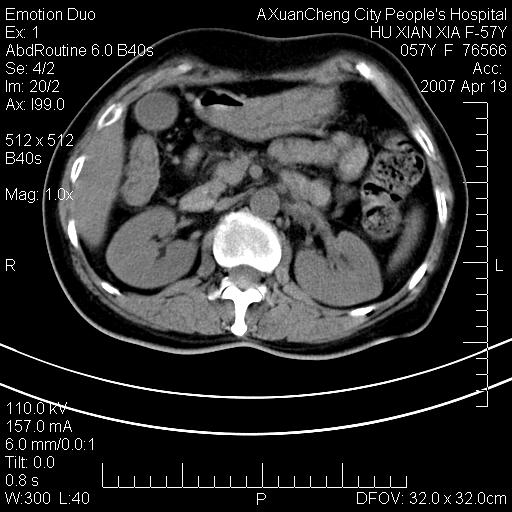

标题: CT7778:[原创]F,57Y腹痛待查,胸片提示肺部占位,应当很典型 [打印本页]

标题: CT7778:[原创]F,57Y腹痛待查,胸片提示肺部占位,应当很典型

胸片提示肺部占位

忽略了,只以为急腹症,应该支持肺癌肾上腺转移,肺癌患者20-30%发生肾上腺转移

考虑双侧肾上腺占位

双肾上腺占位

双侧肾上腺及腹膜后淋巴结增大,考虑转移,建议查原发灶.

双侧肾上腺转移瘤?

双侧肾上腺增大,有分叶,密度均匀,考虑转移建议查原发灶

双肾上腺转移瘤

支持肺癌肾上腺转移,肺癌患者20-30%发生肾上腺转移

双侧肾上腺及腹膜后淋巴结增大,考虑转移,肺转移?

双侧肾上腺结节样肿块,结合肺部肿块,考虑肺癌肾上腺转移。

双侧肾上腺及腹膜后淋巴结增大,结合胸片提示肺部占位,考虑肺癌双侧肾上腺及腹膜后淋巴结转移.